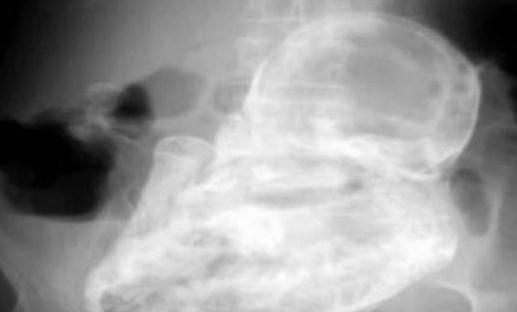

導(dǎo)語:一般人都是“懷胎十月”,而哥倫比亞某醫(yī)院的醫(yī)生們卻遇到了一位懷孕長達40年之久的特殊“孕婦”,這讓醫(yī)院的醫(yī)生護士們震驚不已。

這個孕婦是位82歲的老太太,她因劇烈的腹瀉而到該醫(yī)院就診。在全面的臨床檢查之后,醫(yī)生確定她的腹部并沒有結(jié)石或腫瘤。

不過,接下來的發(fā)現(xiàn)卻讓所有人嚇了一大跳——老太太的子宮外竟然有個未發(fā)育的胎兒,但已經(jīng)死亡了近40年。

這個“石化胚胎”是怎么形成的呢?醫(yī)生解釋稱:“由于胚胎未在子宮里發(fā)育,移動到老婦的腹腔,導(dǎo)致胚胎無法正常生長,因而鈣化形成石胎。”

據(jù)媒體報道,老太太稱,自己40年前曾經(jīng)懷孕,但懷孕過程中常常感到疼痛,于是決定墮胎。由于當時她所居住的村子內(nèi)沒有正規(guī)醫(yī)生,她便向巫醫(yī)求助,讓其為自己墮胎。

在服用了巫醫(yī)的藥后,她發(fā)現(xiàn)肚子不痛了,胎兒也不再動了,因此以為胎兒已經(jīng)被打掉。但實際上,雖然胎兒死了,卻一直留在老人的腹中,這一留就是40年,老太太對此毫不知情。

醫(yī)生表示,這么多年來,老太太沒有因這個胎兒生病,實在是一個奇跡。